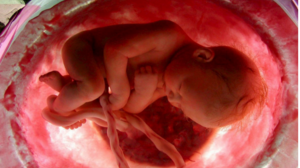

Ασυνήθιστος μηχανισμός φαίνεται πως προστατεύει τα έμβρυα από τον κορωνοϊό ΕΠΙΣΤΗΜΕΣ 03.02.2022 Ασυνήθιστος μηχανισμός φαίνεται πως προστατεύει τα έμβρυα από τον κορωνοϊό

Τι συμβαίνει με τον κορωνοϊό και τα έμβρυα ΕΠΙΣΤΗΜΕΣ 16.04.2021Τι συμβαίνει με τον κορωνοϊό και τα έμβρυα